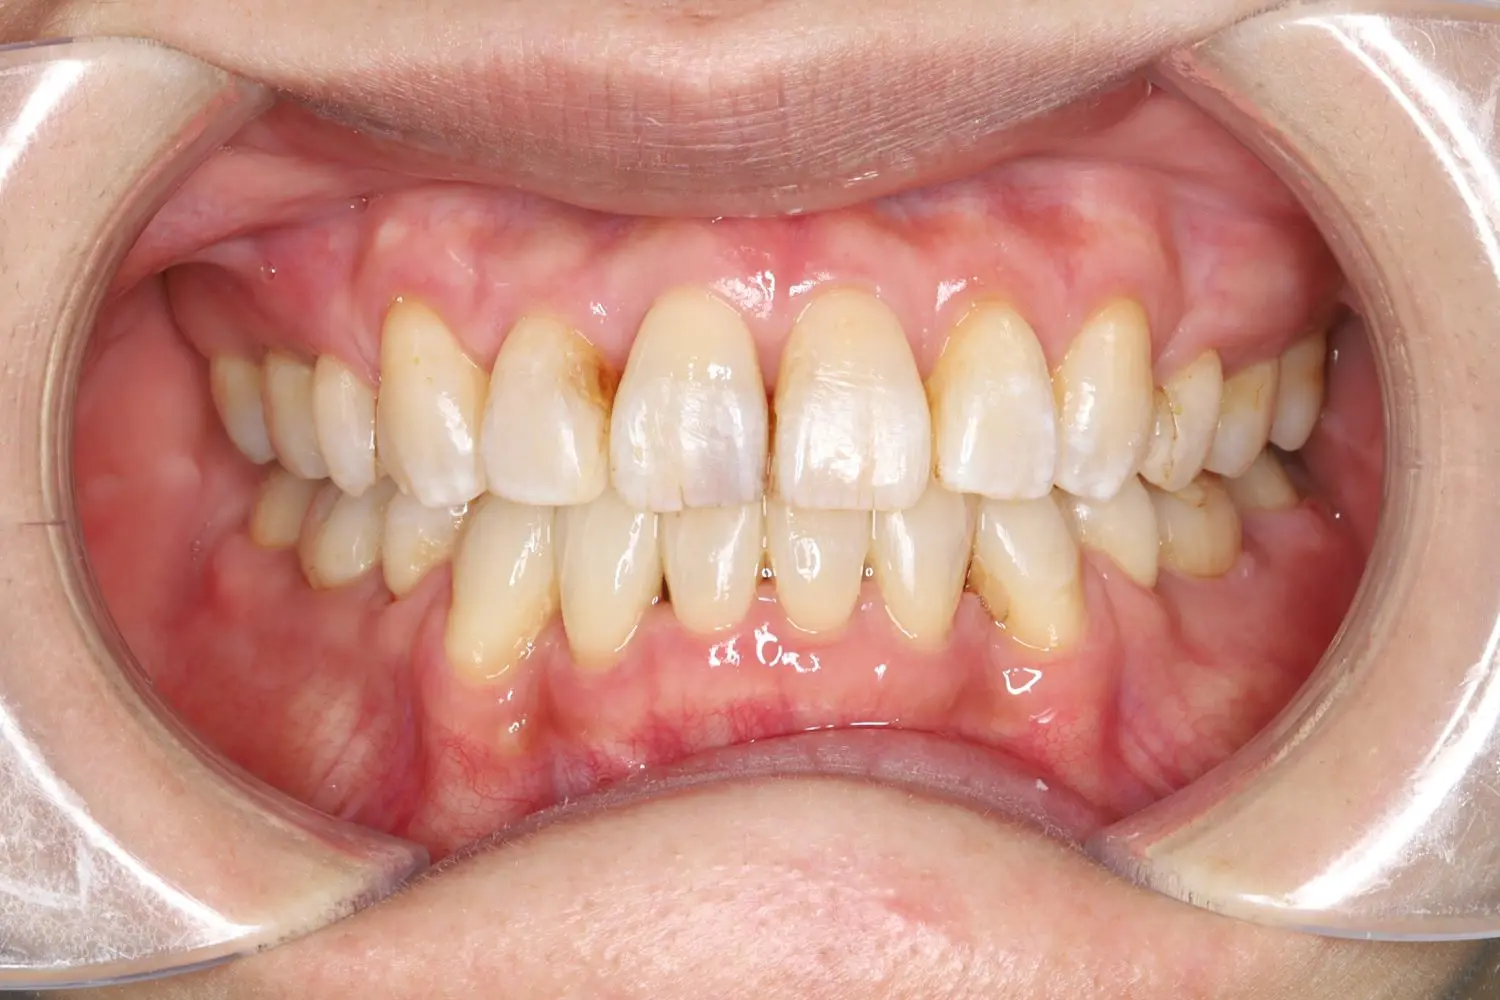

| 年齢 | 20代男性 |

| 主訴 | 前歯でモノが噛めない |

| 治療期間・治療回数 | 1年3か月 |

上顎歯列と下顎歯列の咬合平面を一致させることで非抜歯にて開咬を改善することができました。患者様の協力度が高く、ゴムかけを頑張ってくれたので短期間で動的治療を終了できました。